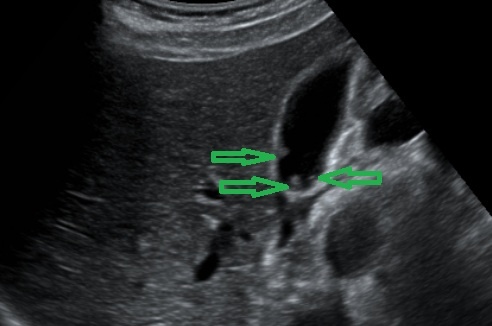

1. УЗИ органов брюшной полости без/с контрастированием (для оценки кровотока в полипе), что является стандартным методом диагностики. Этот способ подходит для оценки динамики роста полипов.

Для холестериновых полипов характерно наличие эффекта реверберации («хвоста кометы») - утолщение стенки желчного пузыря позади наиболее крупных включений, отсутствие кровотока, чаще это множественные округлые или овоидные образования, не смещаемые при изменениях положения тела, без акустической тени.

Злокачественные полипы на УЗИ чаще одиночные и имеют кровоток.